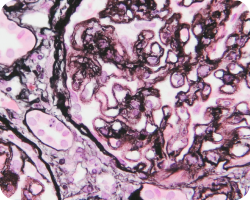

Связь гистологических характеристик по шкале MEST с клиническими аспектами IgA-нефропатии20:

Мезангиальная пролиферация

Image

Течение заболевания у пациентов с мезангиальной пролиферацией (М1) и даже низкой протеинурией ≤ 1 г/день характеризуется схожим прогнозом, как у пациентов со стойкой протеинурией от 1 до 2 грамм в день. Таким образом, несмотря на более низкую экскрецию белка, в первом случае можно говорить о более высоком риске, а также о возможной пользе более ранней иммуносупрессии, потенциально улучшающей сохранение массы нефронов42.